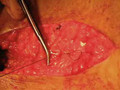

for educational purposes only